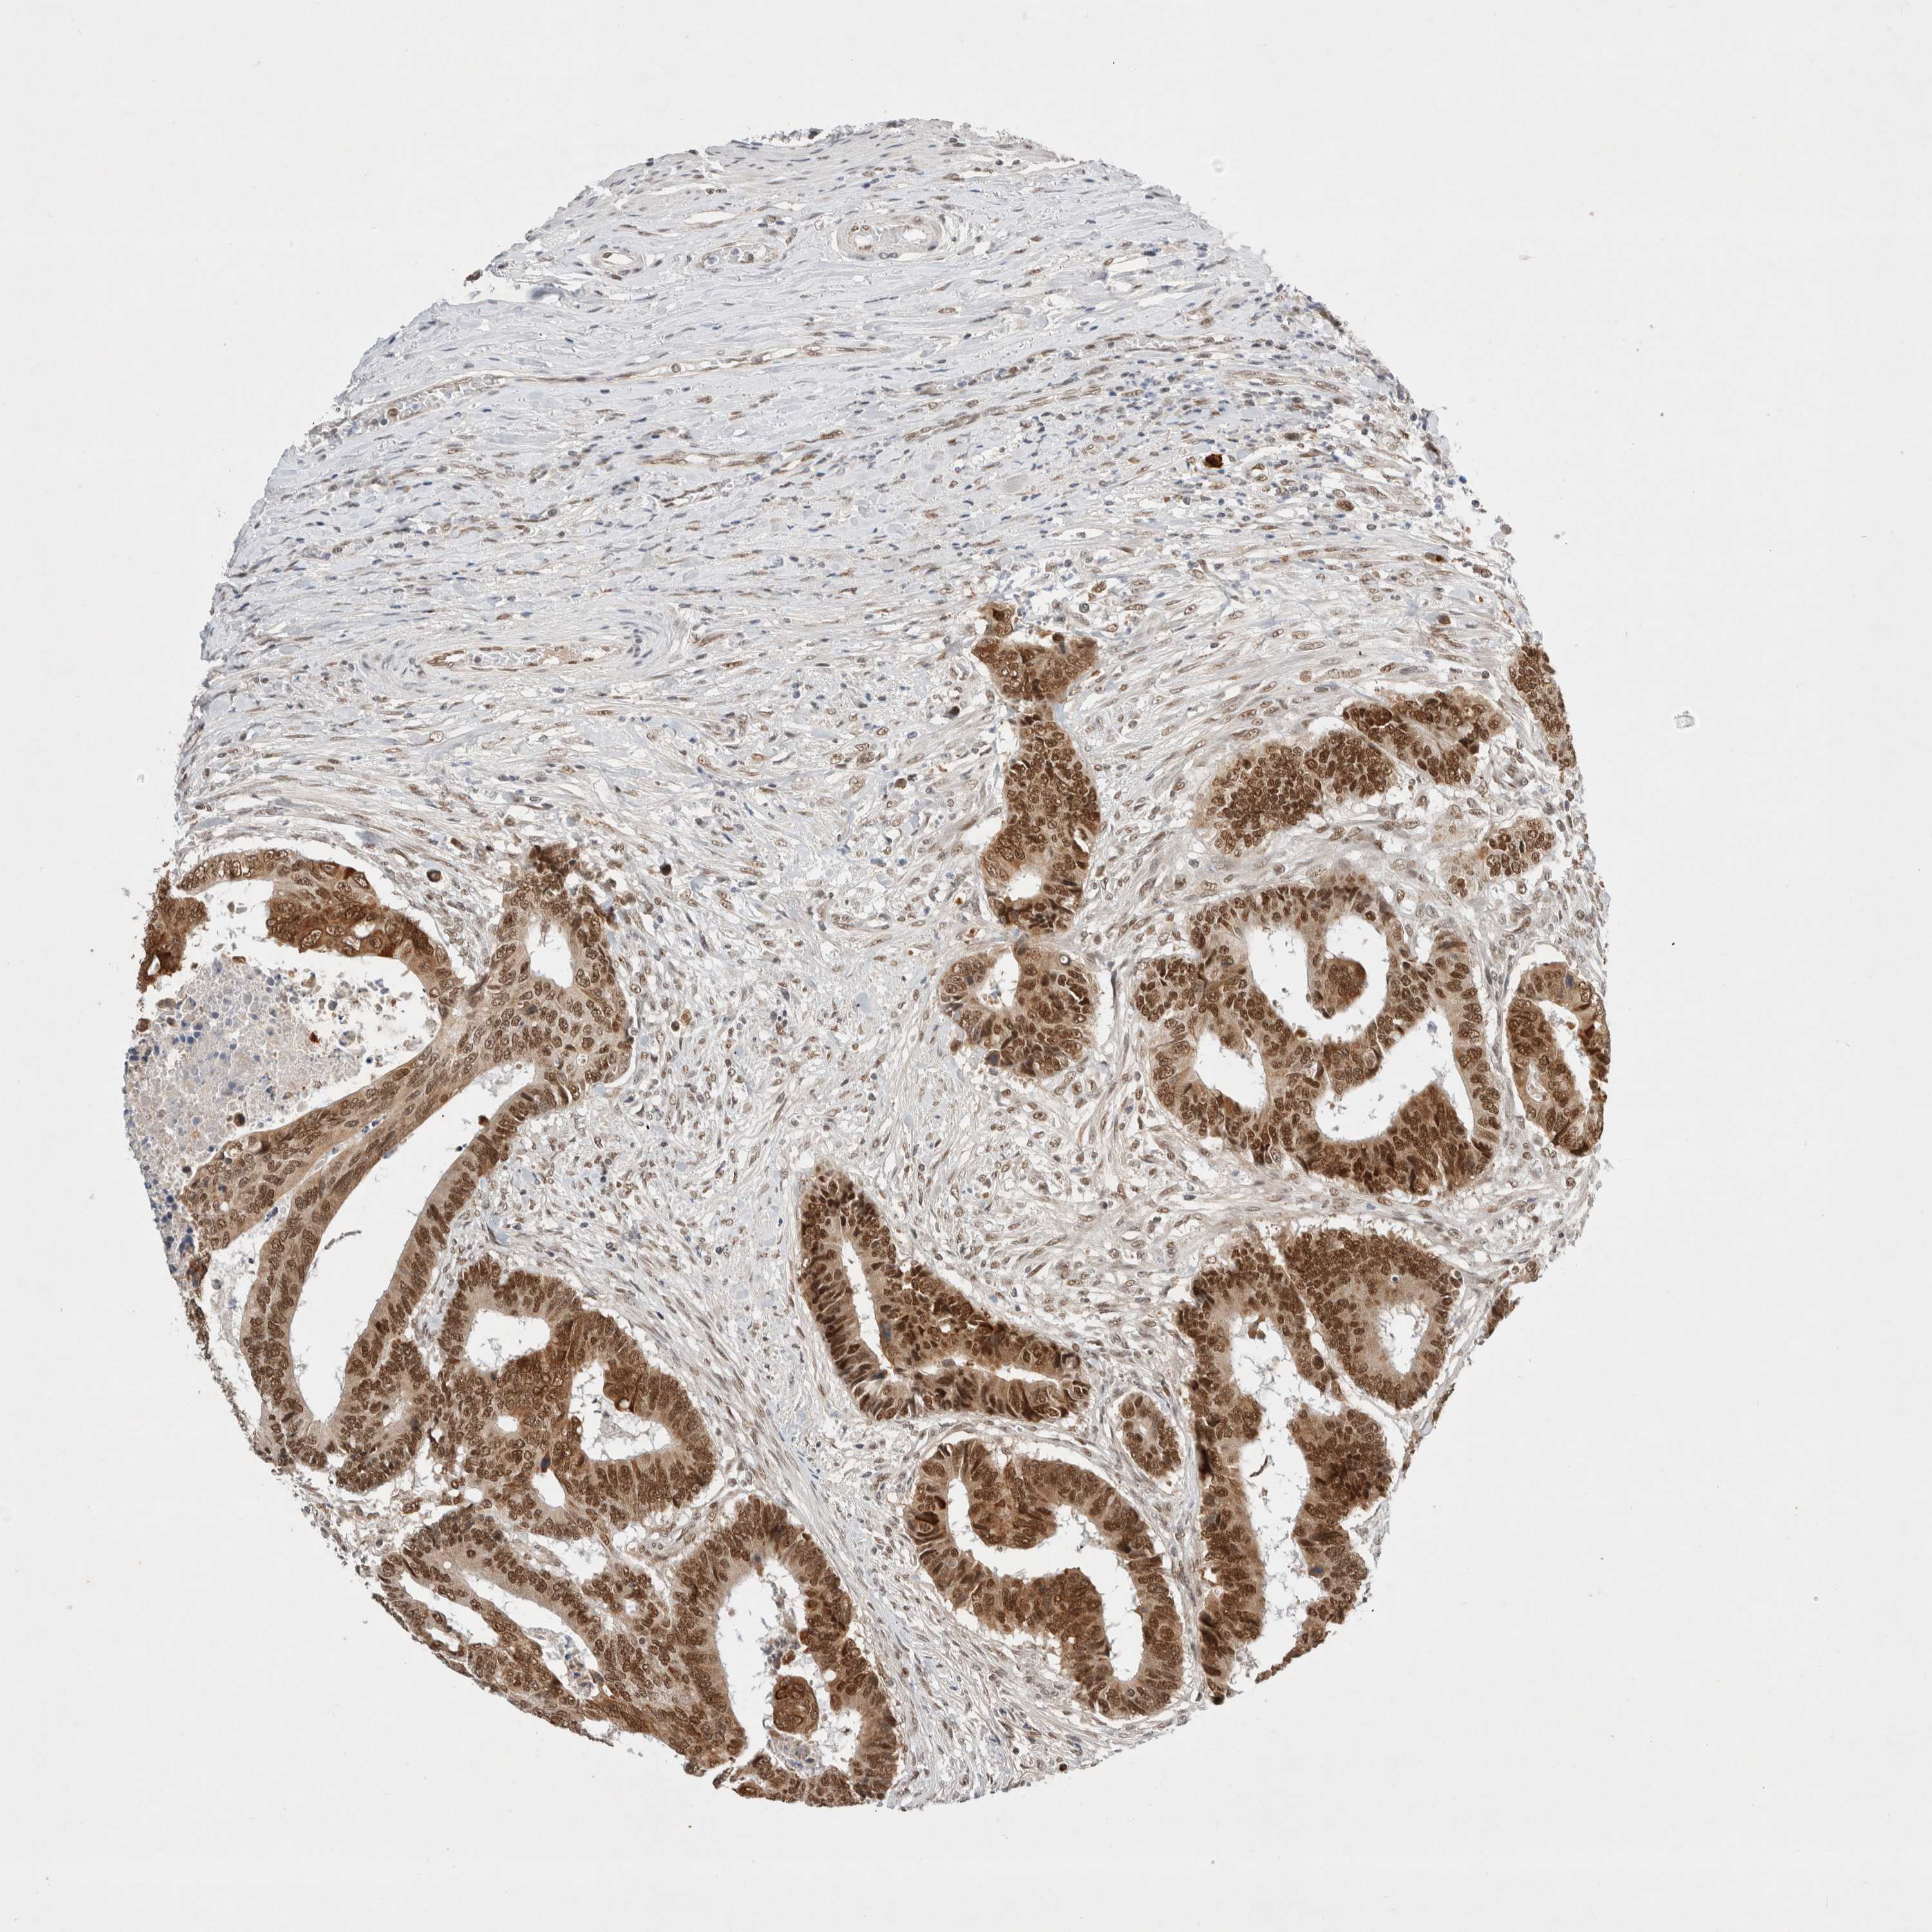

COLON ADENOCARCINOMA (VALIDATION) - Interactive survival scatter ploti

The Survival Scatter plot shows the clinical status (i.e. dead or alive) for all individuals in the patient cohort, based on the same data that underlies the corresponding Kaplan-Meier plots. Patients that are alive at last time for follow-up are shown in blue and patients who have died during the study are shown in red.

The x-axis shows the expression levels (FPKM) of the investigated gene in the tumor tissue at the time of diagnosis. The y-axis shows the follow-up time after diagnosis (years). Both axes are complimented with kernel density curves demonstrating the data density over the axes. The top density plot shows the expression levels (FPKM) distribution among dead (red) and alive patients (blue). The right density plot shows the data density of the survived years of dead patients with high and low expression levels respectively, stratified using the cutoff indicated by the vertical dashed line through the Survival Scatter plot. This cutoff is automatically defined based on the FPKM cutoff that minimizes the p-score. The cutoff can be changed by dragging the vertical line or by entering a cutoff value in the square labeled "Current cut-off".

Under the Survival Scatter plot the p-score landscape (black curve; left axis) is shown together with dead median separation (red curve; right axis). Dead median separation is the difference in median mRNA expression between patients who have died with high and low expression, respectively. It is calculated as follows: median FPKM expression of dead patients with high expression - median FPKM expression of dead patients with low expression. This is intended to aid the user in visually exploring custom cutoffs and the associated p-scores and dead median separation.

Individual patient data is displayed and can be filtered by clicking on one or more of the category buttons on the top of the page. Categories describing expression level and patient information include: high, low, alive, dead, female, male and tumor stages. The scale of the x-axis can be toggled between linear and log-scale by clicking on the "x log" button. Mouse-over function shows TCGA ID, patient information and mRNA expression (FPKM) for each patient.

& Survival analysisi

Kaplan-Meier plots summarize results from analysis of correlation between mRNA expression level and patient survival. Patients were divided based on level of expression into one of the two groups "low" (under cut off) or "high" (over cut off). X-axis shows time for survival (years) and y-axis shows the probability of survival, where 1.0 corresponds to 100 percent.

GTF2I is not prognostic in Colon Adenocarcinoma (validation)

Best expression cut offi

Based on the FPKM value of each gene, patients were classified into two groups and association between prognosis (survival) and gene expression (FPKM) was examined. The best expression cut-off refers the FPKM value that yields maximal difference with regard to survival between the two groups at the lowest log-rank P-value. Best expression cut-off was selected based on survival analysis .

When clicking on this number, the vertical dashed line indicating cut-off, the interactive survival plot, and the Kaplan-Meier curve will be adjusted to show results based on the best expression cut-off.

: 131.2

Median expressioni

Median expression refers to the median FPKM value calculated based on the gene expression (FPKM) data from all patients in this dataset. When clicking on this number, the vertical dashed line indicating cut-off, the interactive survival plot, and the Kaplan-Meier curve will be adjusted to show results based on the median expression.

: N/A

P scorei

Log-rank P value for Kaplan-Meier plot showing results from analysis of correlation between mRNA expression level and patient survival.

N/A

5-year survival highi

5-year survival for patients with higher expression than the expression cutoff.

For melanoma and glioma, 3-year survival is shown.

5-year survival lowi

5-year survival for patients with lower expression than the expression cutoff.

TCGA RNA samplesi

RNA-seq data is reported as average FPKM (number Fragments Per Kilobase of exon per Million reads), generated by the The Cancer Genome Atlas (TCGA) .

Normal distribution across the dataset is visualized with box plots, shown as median and 25th and 75th percentiles. Points are displayed as outliers if they are above or below 1.5 times the interquartile range. FPKM values of the individual samples are presented next to the box plot.

Average pTPM 122.0

Number of samples 486